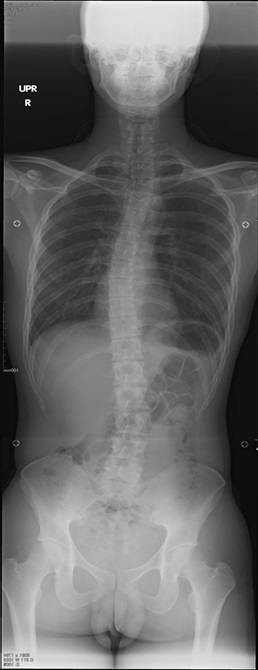

脊柱を正面から見て左右に曲がっている状態を脊柱側弯症といいます。

背骨を背面から見たときの背骨のカーブの大きさを表す角度です。

側弯症の程度を表すのに用いられます。

単純レントゲン画像で背骨のカーブの一番上の骨と一番下の骨を線で結び計測します。

単純X線検査

側弯症の検査は、全脊椎の単純レントゲン画像を撮影します。

アレックス脊椎クリニックでは脊椎全体を見れるレントゲン装置を導入しています。

一度の撮影で立った姿勢の背骨の様子がわかります。